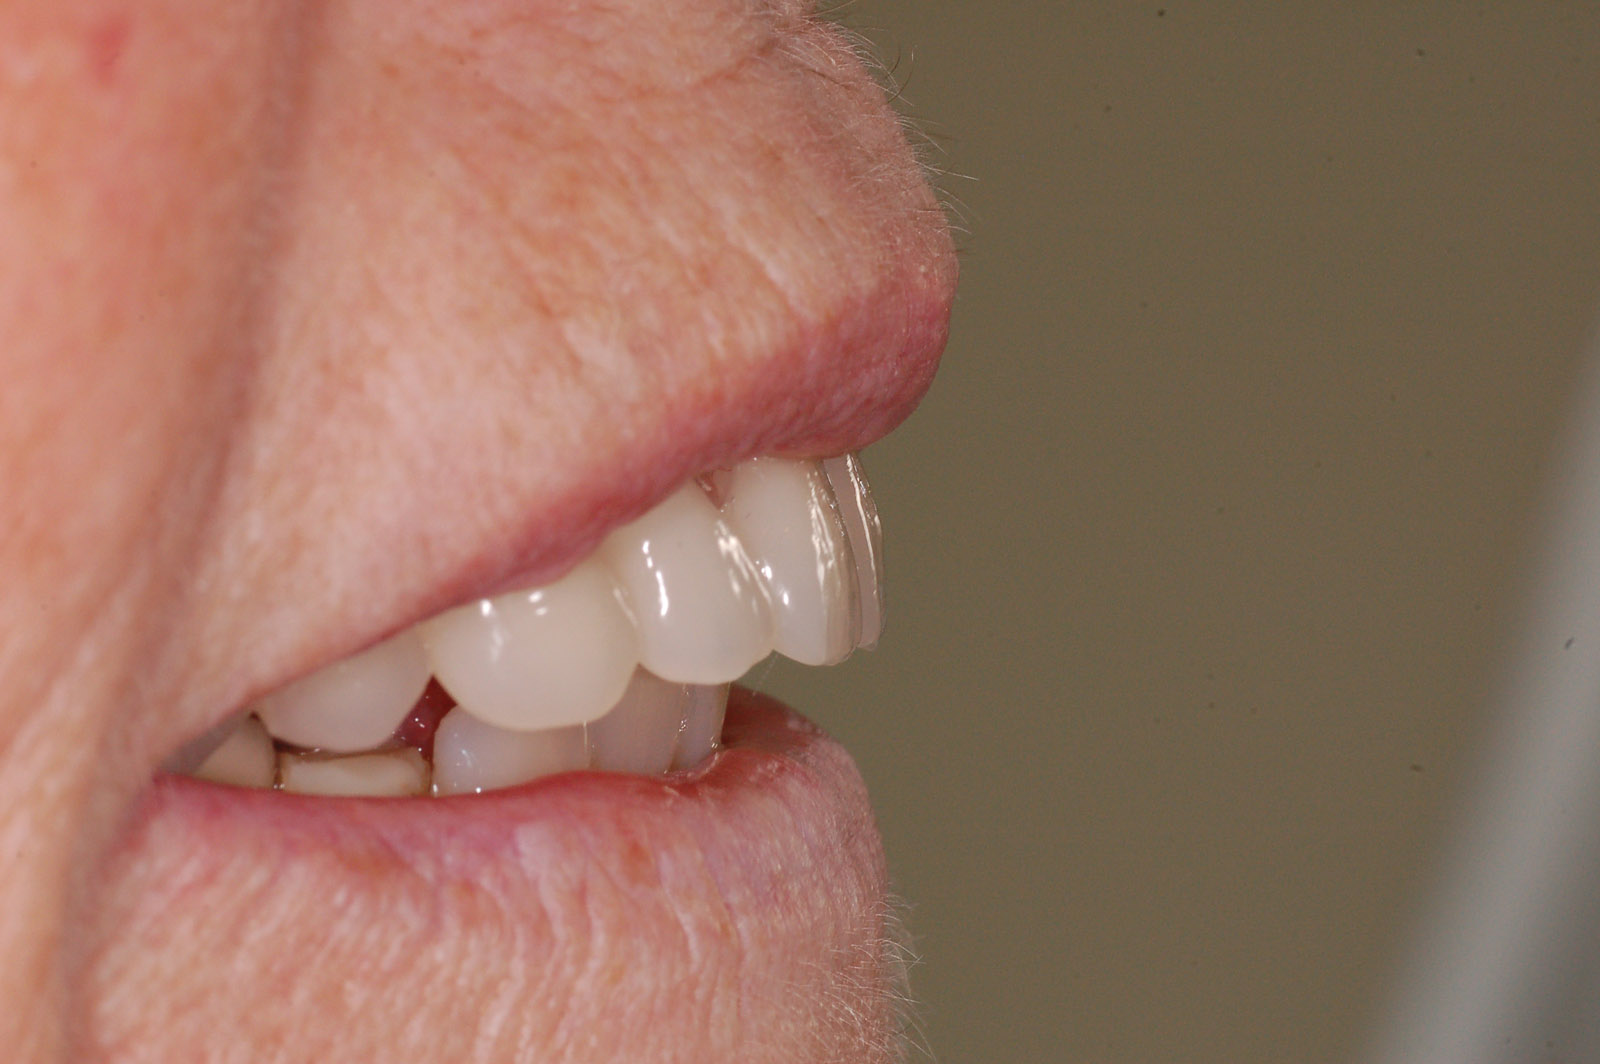

A thorough extra-oral examination, including the patientís profile and lip support, was carried out (Figure 1).

The patient was very pleased with the final aesthetic result, which improved her confidence when talking to people. She was once again able to enjoy chewing food without discomfort (Figure 14).